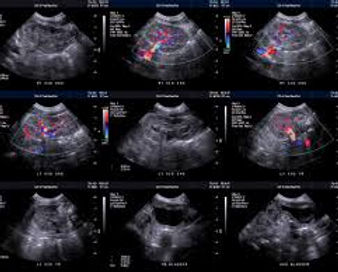

Ecografia scrotale con Doppler

Esame ecografico di alta precisione per la valutazione di testicoli, epididimo e funicolo spermatico.

Il Doppler consente di studiare la vascolarizzazione, identificando patologie come varicocele, idrocele, cisti o lesioni testicolari.

È indicato anche nei controlli di infertilità maschile o dopo traumi scrotali.